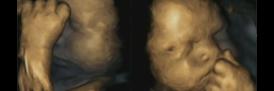

Left-handed fetuses could show effects of maternal stress on unborn babies

Fetuses are more likely to show left-handed movements in the womb when their mothers are stressed, according to new research.